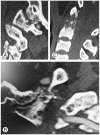

Methods: Upper cervical lesions in nine patients undergoing hemodialysis were surgically treated. Mean age at surgery was 61.6 years (range, 52-68 years), and the mean follow-up period was 45.4 months (range, 2-98 months). Patients had undergone hemodialysis for an average of 25.3 years (range, 16-40 years) at surgery. Seven patients with destructive spondyloarthropathy (DSA) of the upper cervical spine were treated with atlantoaxial or occipitocervical fixation. Two patients with retro-odontoid pseudotumors were treated with C1 posterior arch resection alone. Japanese Orthopedic Association (JOA) scores for cervical myelopathy, postoperative complications, postoperative radiography, and preoperative and postoperative occipital pain were evaluated.

Results: Mean preoperative and postoperative JOA score was 3.7 and 8.1, respectively. The seven patients with DSA had severe preoperative occipital pain that disappeared postoperatively. Postoperative radiography showed solid bone union in DSA cases and no instability in pseudotumor cases.